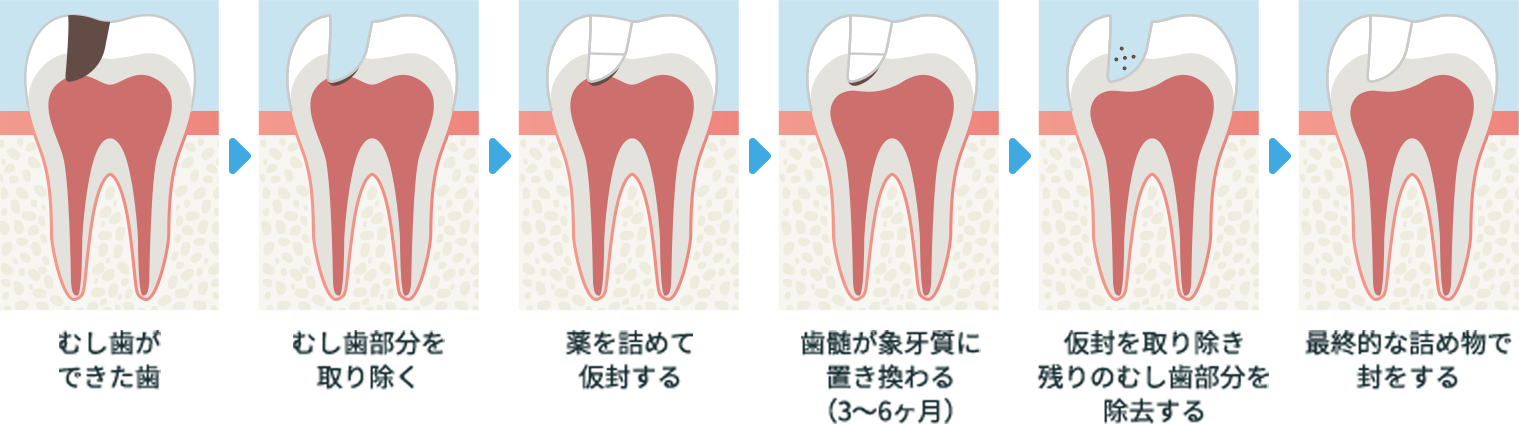

むし歯治療

(歯髄温存療法:覆髄、断髄)

神経を残してむし歯の感染部分を取り残さないように取り除くことで治療します。健康な歯をできるだけ残せるように、拡大鏡を使用して治療を行います。

横スクロールで確認いただけます。